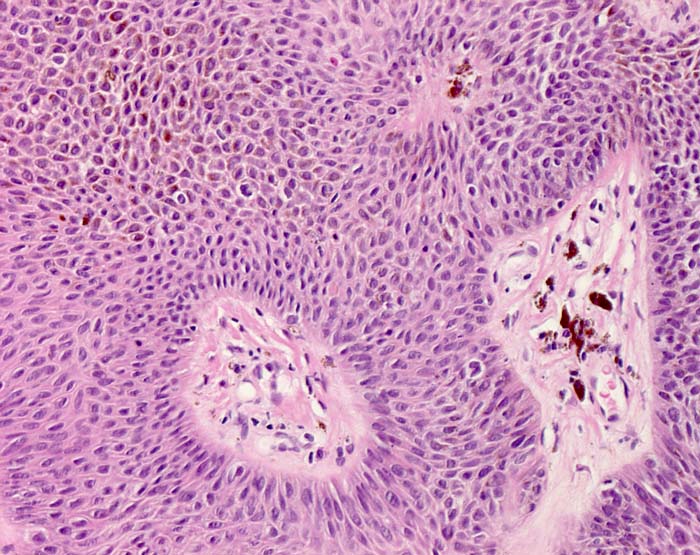

Histologie:

Die grosse makroskopische Vielgestaltigkeit widerspiegelt sich auch in einer variablen Histologie. Unterschieden werden mehrere histologische Subtypen der seborrhoischen Keratose: Hyperkeratotischer Typ (> 3435), akanthotischer Typ (Kurspräparat), klonaler Typ (> 7284) (> 7285), irritierte seborrhoische Keratose (> 3353) (> 3356). Typisch für seborrhoische Keratosen sind umschriebene Wirbelbildungen von Tumorzellen, sogenannte squamous eddies (> 8065). Der retikuläre Typ (> 7838) entwickelt sich in chronisch UV exponierter Haut meist im Gesicht und geht oftmals hervor aus einer solaren Lentigo (> 7839)

Morphologische Merkmale:

• Erhabener (=exophytischer) Tumor

• Verdickte Epidermis (Akanthose)

• Keratingefüllte Epidermisinvaginationen und Hornzysten mit konzentrisch geschichteten Hornlamellen.

• Vernetzte Zellstränge bestehend aus monomorphen basaloiden zytoplasmaarmen Plattenepithelzellen.

• Herdförmige starke braune Pigmentierung der Tumorzellen.

• Perivaskulär betonte, oberflächlich dermale lymphohistiozytäre Entzündung mit Melanophagen. Das sollte der Kliniker dem Pathologen mitteilen: